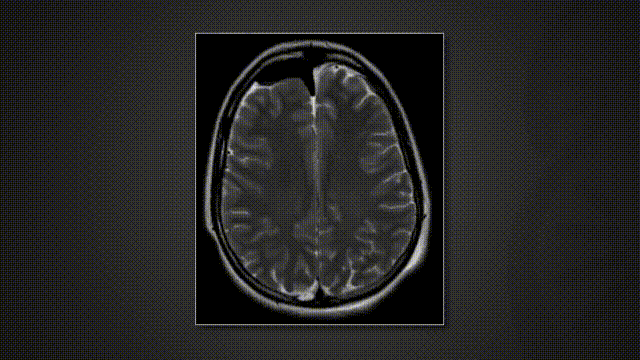

INC国际教授团队经多学科联合讨论后,决定在安全边界内实施二期最大程度切除。二期手术选择左侧远外侧入路开颅,联合C1半椎板切除,最终实现了残余肿瘤的完整切除。患者于术后第六天顺利出院,仅遗留轻度面部感觉异常,随访过程中逐渐恢复正常。术后及术后六个月的影像学复查均证实肿瘤全切,未见并发症。

术后影像